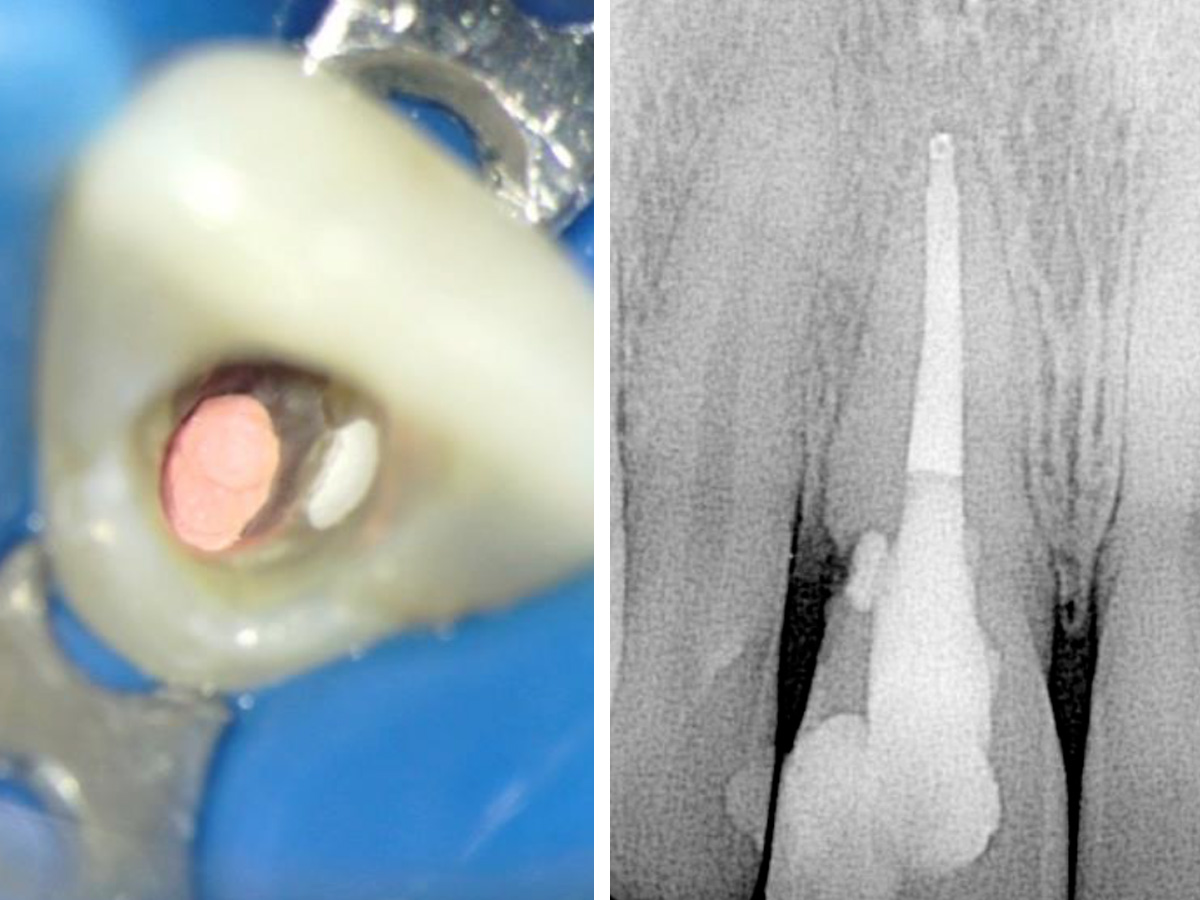

Abbildung 4

Der geöffnete Zugang zeigt die Gutta-Percha im koronalen Kanal und das BC Putty im resorptiven Defekt. Das Röntgenbild zeigt die Situation direkt nach der Behandlung.

Als die Patientin nach zwei weiteren Wochen wiederkam, war keinerlei Fistelbildung zu diagnostizieren, das biokeramische Putty war immer noch an der modellierten Stelle vorhanden und schien den Defekt gut zu versiegeln. Der Wurzelkanal wurde fertiggestellt und die Zugangskavität mit einem Komposit versiegelt (Abb. 4).